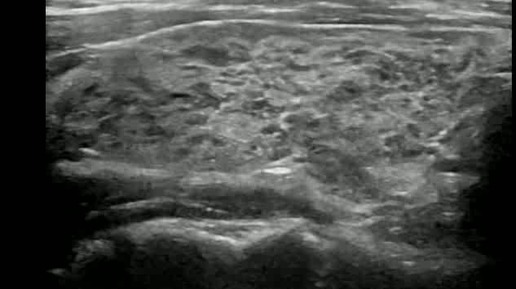

Видео к статье "Стратификация узлов щитовидной железы. TI-RADS-3" https://dzen.ru/a/Zv4svErHVi-eImKZ

Ультразвуковые находки от врача УЗД Зорина Я.П.